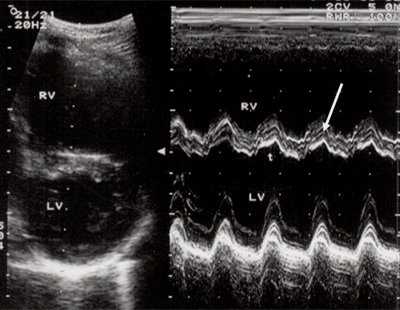

Характерными особенностями выраженной объемной перегрузки правого желудочка являются дилатация желудочка, при которой толщина миокарда не превышает верхней границы нормы, увеличение правого предсердия, парадоксальный характер движения межжелудочковой перегородки и увеличение амплитуды движения трикуспидального клапана (рис. 2, 3).

Рис. 3. Объемная перегрузка правого желудочка при дефекте межпредсердной перегородки. В- и М-сканирование. Стрелкой показан парадоксальный характер движения межжелудочковой перегородки.

Для левого желудочка признаком объемной перегрузки являются увеличение полости левого предсердия и желудочка, а также экскурсии межжелудочковой перегородки и миокарда задней стенки левого желудочка (рис. 4).

Рис. 4. Объемная перегрузка левых отделов сердца. В- и М-сканирование. Отмечается усиление экскурсии межжелудочковой перегородки и миокарда задней стенки левого желудочка.

IVS - межжелудочковая перегородка, MLV - миокард левого желудочка, LV и RV - левый и правый желудочек.